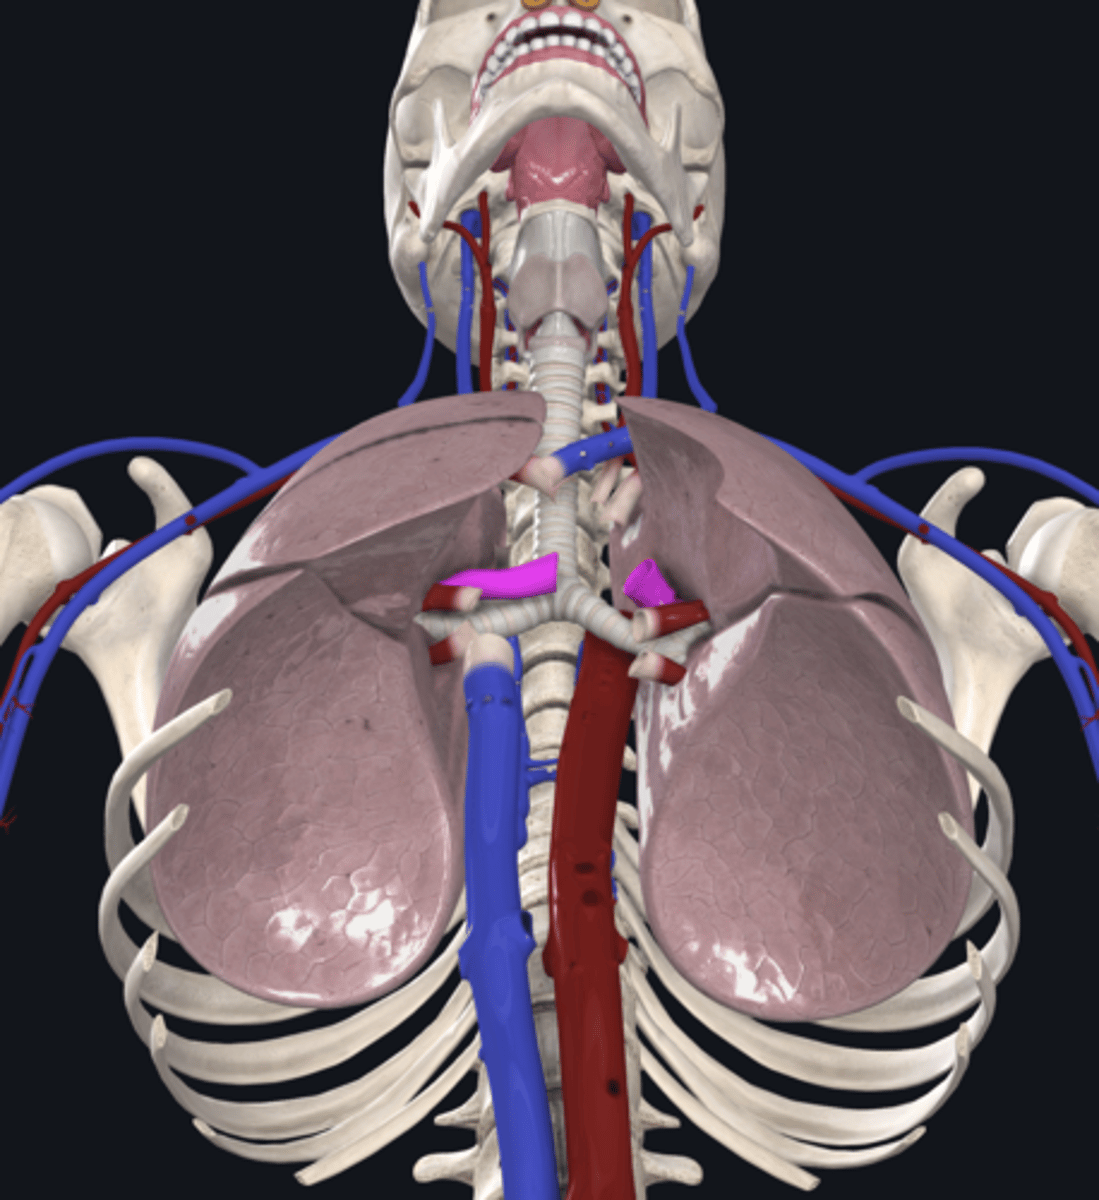

right lung

superior lobe of right lung

middle lobe of right lung

inferior lobe of right lung

left lung

superior lobe of left lung

inferior lobe of left lung

pulmonary artery

pulmonary vein

hilum of right lung

hilum of left lung

right main bronchus

left main bronchus

lobar bronchi